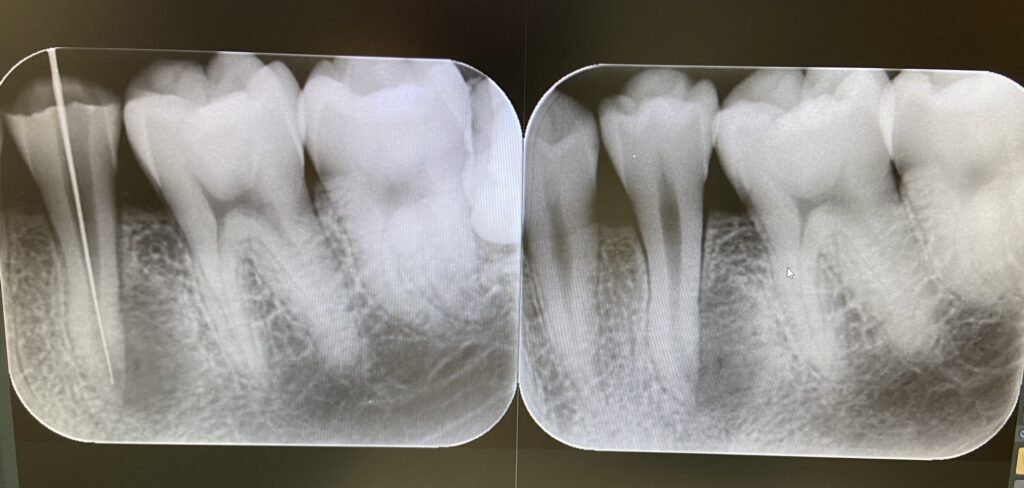

デンタルエックス線写真は、お口全体は分かりませんが、細かなところをみるのに適しています。

パノラマエックス線写真でお口全体をチェックして、細かなところをデンタルエックス線写真でチェックするという方法が行われますが、それでも初期虫歯が写し出されないこともしばしば起こります。

レントゲン写真なら確実にわかるように思われがちですが、初期虫歯では必ずしもそうではないというところも、虫歯の判断を難しくしています。